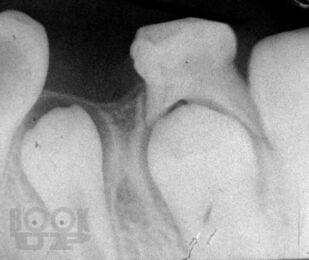

Терапевтическая стоматология детского возраста

Учебное пособие составлено в соответствии с учебным планом по терапевтической стоматологии детского возраста. В нем описаны методики обследования зубочелюстной системы в детском возрасте, освещены особенности течения у детей патологических процессов в зубах, тканях пародонта и слизистой оболочке полости рта, проявления инфекционных заболеваний в челюстно-лицевой области. Детализировано своеобразие лечебной тактики при основных стоматологических заболеваниях, исходя из анатомо-физиологических особенностей детского организма. Отражены пути организации диспансеризации детского населения у стоматолога и плановой санации полости рта у детей.